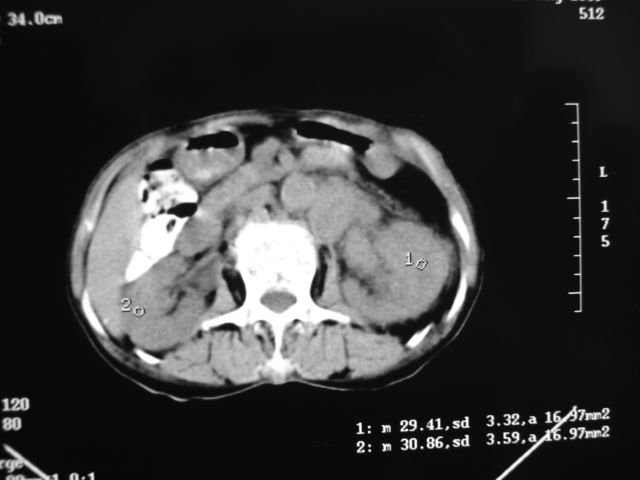

同事奶奶,73岁,腹痛一年,夜晚较重,潜血+++,拒绝增强,考虑左肾ca并腹膜后转移;请各位老师帮忙看看,谢谢!

左肾癌侵及输尿管上段,腹膜后多发淋巴结转移,脾脏钙化灶。至于潜血+++,要考虑消化道病变,本次ct片肠腔未见明显异常。

潜血+++是尿还是便?如果是便,则考虑肾癌侵犯降结肠可能。

1)考虑左肾癌侵犯肾盂并腹膜后淋巴结转移。2)脾脏钙化灶。